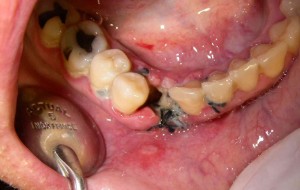

Absceso facial

Un absceso facial es una acumulación de pus en los tejidos faciales debido a una infección bacteriana.

Los pacientes pueden notar hinchazón, dolor intenso, fiebre y enrojecimiento en el área afectada.

El tratamiento incluye el drenaje quirúrgico del absceso y el uso de antibióticos para combatir la infección.